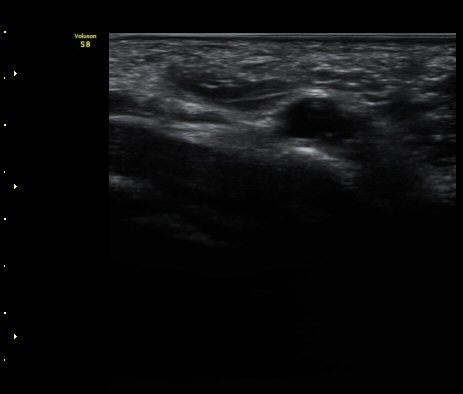

ÃÊÀ½ÆÄ °Ë»ç